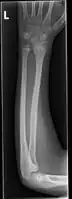

Front view of displaced fractured radius and ulna at wrist -

Side view of displaced fractured radius and ulna at wrist -

Front view of bowing fractured radius and ulna -

Side view of bowing fractured radius and ulna